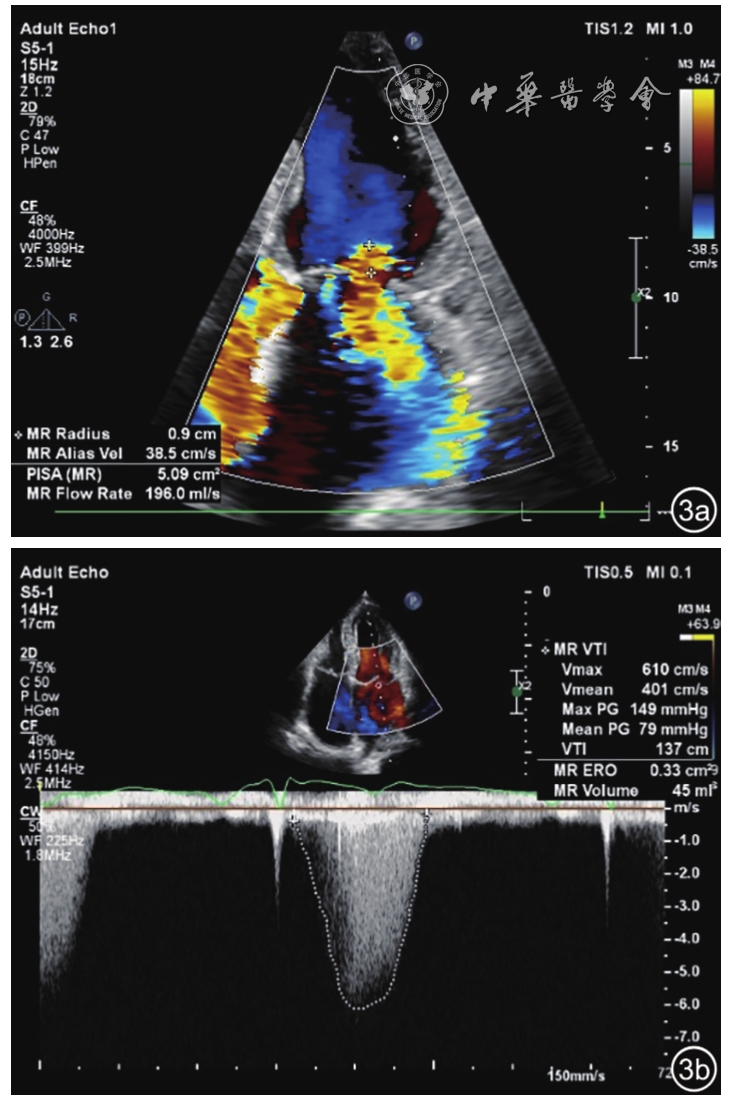

1. 反流面积法12:(1)轻度反流:反流束面积<4 cm2或20%左心房面积;(2)中度反流:反流束面积4~10 cm2或20%~40%左心房面积;(3)重度反流:反流束面积>10 cm2或40%左心房面积(图1)。然而,反流面积的大小与反流程度并无高度的相关性,易受血流动力学变化的影响,例如一些血压偏低伴有急性重度FMR的患者,因其左心房压力升高,仅显示少量的偏心性反流面积;而一些高血压伴有轻度FMR的患者,反而可以出现较大的反流面积。因此,反流面积法并不能精确评估FMR的程度。

图1 二维超声心动图测量二尖瓣反流束面积和左心房面积。图a示二尖瓣反流束面积为15.2 cm2;图b示为左心房面积为37.5 cm2